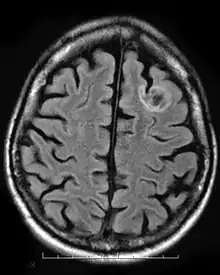

A dysembryoplastic neuroepithelial tumor is a rare, benign tumor that affects children and teenagers under the age of twenty. The tumor occurs in the tissue covering the brain and spinal cord. The symptoms of the tumor are dependent on its location, but most children experience seizures that cannot be controlled by medication. DNT is usually treated through invasive surgery and the patients are usually capable of recovering fully, with little to no long-term effects.[9]

Neuroepithelial cysts, also known as colloid cysts, develop in individuals between the ages of 20 and 50 and is relatively rare in individuals under the age of twenty. The cysts are benign tumors that usually appear in the anterior third ventricle. The cysts occur in the epithelium putting their patients at risk for obstructive hydrocephalus, increased intracranial pressure, and rarely intracystic hemorrhage. This results from the cysts enlarging by causing the epithelium to secrete additional mucinous fluid. The cysts are usually found incidentally or if patients become symptomatic presenting with the symptoms of hydrocephalus. The larger cysts are operated on while smaller cysts that are not obstructive can be left alone.[10]

Oligodendroglial tumors manifest in glial cells, which are responsible for supporting and protecting nerve cells in the brain. The tumor develops over oligodendrocytes and is usually found in the cerebrum around the frontal or temporal lobes. The tumors can either grow slowly in a well-differentiated manner delaying the onset of symptoms, or they can grow rapidly to form an anaplastic oligodendroglioma. The symptoms for this type of tumor include headaches and visual problems. Additionally, blockage of ventricles could cause buildup of cerebral spinal fluid resulting in swelling around the tumor. The location of the tumor may also affect the symptoms since frontal lobe tumors can cause gradual mood or personality changes while temporal lobe tumors result in coordination and speech problems.[11]